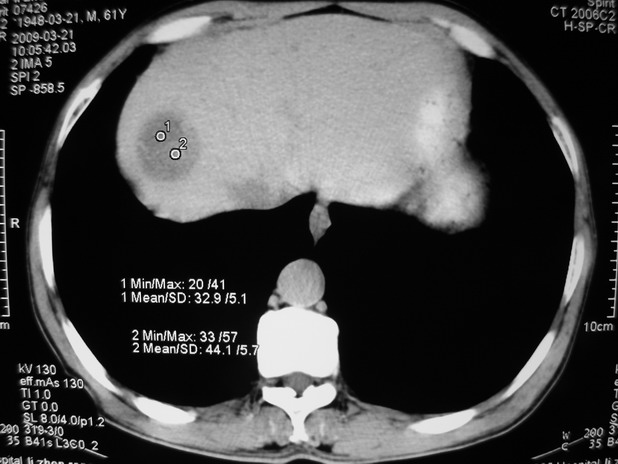

以下是引用余辉在2009-3-21 21:36:00的发言:[br]图像太乱了,建议楼主直接将强化数据按顺序列出来,病灶位置较表浅薄,有肝炎病史,灶内实性成分有显著强化,动脉期约60hu,考虑肝癌可能性大,进一步检查。